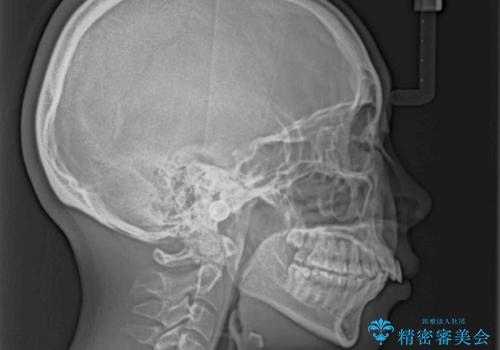

上顎前突で口が閉じにくい ワイヤー装置での抜歯矯正

骨格的に上顎歯列が前方位にあり、口元の突出感が顕著な状態で、上下左右の第一小臼歯4本を抜歯して、ワイヤー装置での抜歯矯正を行うこととしました。

奥歯の咬み合わせ改善のために、アンカースクリューの使用と上顎左右第一小臼歯の抜歯のタイミングをコントロールして、理想的な咬み合わせに仕上げていくこととしました。